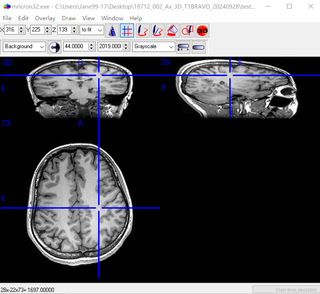

mricron可视化头部MR结构像(GE机器扫描),图像变形严重

mricron可视化头部MR结构像(GE机器扫描),图像变形严重,请问是为什么呢?谢谢~

在使用 mricron 可视化头部MR结构像时遇到图像变形严重的问题,可能是由以下几个原因导致的:

1. 扫描设备问题:MR扫描设备(如GE机器)在扫描过程中可能会出现一些技术故障或参数设置不当的情况,导致图像变形。这可能是硬件问题或操作不当造成的。

2. 图像重建和处理问题:MR图像需要经过重建和处理后才能进行可视化。如果在这个过程中出现了错误或参数设置不当,也可能导致图像变形。

3. 可视化软件问题:mricron软件在处理图像时,如果软件本身存在缺陷或与扫描设备兼容性问题,也可能导致图像变形。